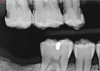

Fig 31. Preoperative radiograph showing deep caries in canal. Restoration prior to endodontic therapy is required.

Figure 31